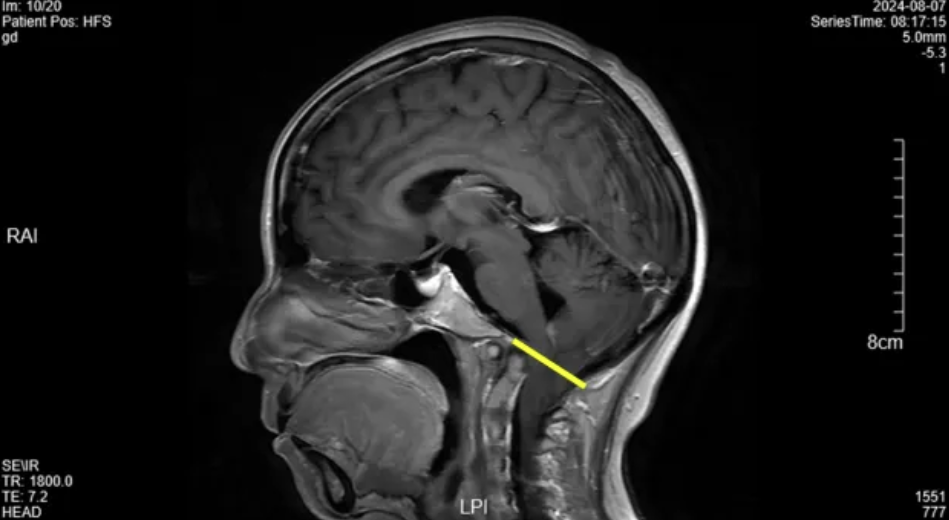

医生原本计划完善气管镜和肺功能激发试验,此时立即转换思路、调整诊断方向,安排患者完善头颅MR增强,结果提示颅底凹陷伴小脑扁桃体疝。

图: 8月7日我院头颅MR增强结果。黄线显示为枕骨大孔平面,小脑扁桃体下端通过枕骨大孔平面向下移位 ≥ 5 mm,提示小脑扁桃体疝。

这个结果是否能解释患者的呛咳呢?患者存在颅颈交界区畸形情况,小脑扁桃体疝患者在神经外科、神经内科比较常见,因此主管医生联系了我院神经外科。从神经外科了解到,小脑扁桃体疝女性多于男性,病程方面,从出现症状到入院时间为6周-30年,平均4.5年,常见症状无特异性,可表现为颈部疼痛、面部感觉异常、共济失调、眼球震颤、四肢感觉异常、饮水呛咳、声音嘶哑。令人惊讶的是,到目前为止,这位患者感知到的唯一症状就是“呛咳”。